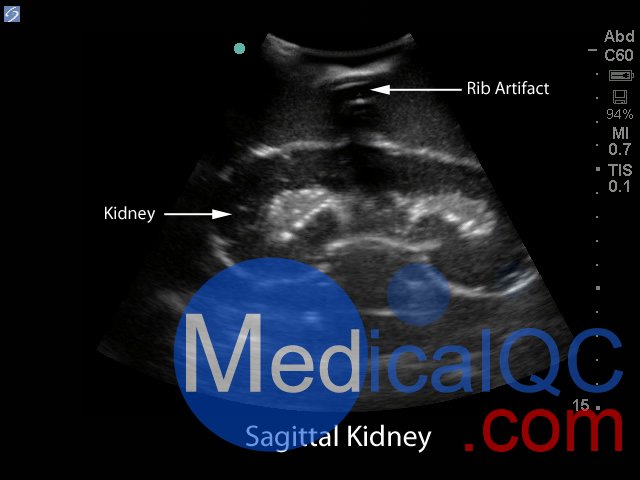

Blue Phantom的經(jīng)皮腎穿刺活檢超聲訓(xùn)練模型允許使用芯針穿刺活檢或穿刺穿刺技術(shù)重復(fù)進(jìn)行針頭活檢。該模型提供了解剖學(xué)上正確的成年男性軀干,其超聲組織模塊包含皮膚,肋骨和右腎以及周圍組織。腎臟的內(nèi)部和外部結(jié)構(gòu)在其逼真度和成像特性方面極佳,并且包含腎皮質(zhì),腎髓質(zhì)以及主要和次要的花萼。使用與真實(shí)人體組織的聲學(xué)特征相匹配的Blue Phantom模擬組織構(gòu)造而成,因此,當(dāng)您在我們的訓(xùn)練模型上使用超聲系統(tǒng)時(shí),您將獲得與在臨床環(huán)境中對患者進(jìn)行成像所期望的相同質(zhì)量。

超聲成像和程序技能包括;使用超聲系統(tǒng)控制,換能器定位和移動(dòng),識(shí)別腎解剖結(jié)構(gòu),在腎活檢期間避免肋骨出現(xiàn),避免肋骨出現(xiàn),使用超聲將目標(biāo)對準(zhǔn)腎活檢的適當(dāng)位置并執(zhí)行超聲引導(dǎo)的腎活檢程序。使用配置了適當(dāng)?shù)哪I臟活檢換能器的任何超聲成像系統(tǒng),此超聲動(dòng)手訓(xùn)練模型將表現(xiàn)良好。這種超聲體模模型非常適合包括腎臟科,介入放射學(xué),外科手術(shù),外科手術(shù)訓(xùn)練計(jì)劃,超聲訓(xùn)練計(jì)劃,模擬中心,外科技能中心,醫(yī)學(xué)教育設(shè)施,腎臟活檢設(shè)備制造商和超聲制造商進(jìn)行超聲教育和演示的專業(yè)。

具有包含皮膚,肋骨和右腎以及周圍組織的超聲組織模塊,解剖學(xué)上正確的成年男性軀干

腎臟的內(nèi)部和外部結(jié)構(gòu)在其逼真度和成像特性方面極佳,并且包含腎皮質(zhì),腎髓質(zhì)以及主要和次要的花萼